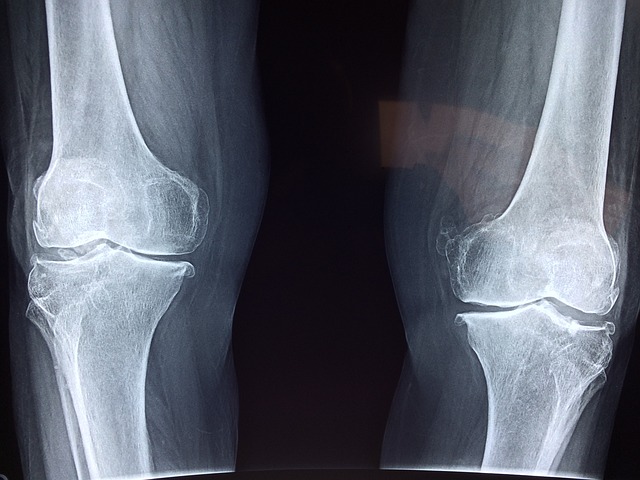

- X-레이: 슬개골과 대퇴골 사이의 정렬 상태를 평가하고, 뼈의 구조적 문제가 있는지 확인합니다. 그러나 X-레이는 연골 자체는 보여주지 않습니다.

- 연골의 지속적인 마모: 연골연화증이 진행되면, 슬개골과 대퇴골 사이의 연골이 계속해서 마모될 수 있습니다. 이는 연골이 점차 얇아지고 손상되면서, 뼈와 뼈가 직접 마찰하는 상황으로 이어질 수 있습니다.

- 관절염 발전: 연골연화증은 골관절염을 비롯한 다른 유형의 관절염으로 발전할 위험이 있습니다. 연골의 지속적인 마모와 염증은 관절의 영구적인 손상을 초래할 수 있습니다.